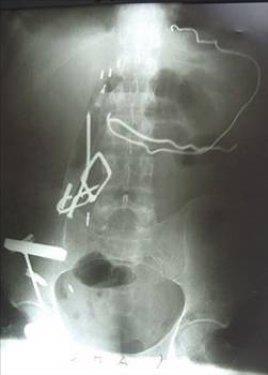

5. İran'da, korkusunu bastırmak ve sıkıntılarından kurtulmak için madeni nesneleri yiyen genç kızın karnından ameliyatla yarım kilogram ağırlığında metal parçalar çıkarıldı.

İran'da, korkusunu bastırmak ve sıkıntılarından kurtulmak için madeni nesneleri yiyen genç kızın karnından ameliyatla yarım kilogram ağırlığında metal parçalar çıkarıldı.

6. 17 yaşındaki genç kızın karnından çıkarılan madeni nesnelerin arasında jilet ve çiviler de bulundu.

17 yaşındaki genç kızın karnından çıkarılan madeni nesnelerin arasında jilet ve çiviler de bulundu.